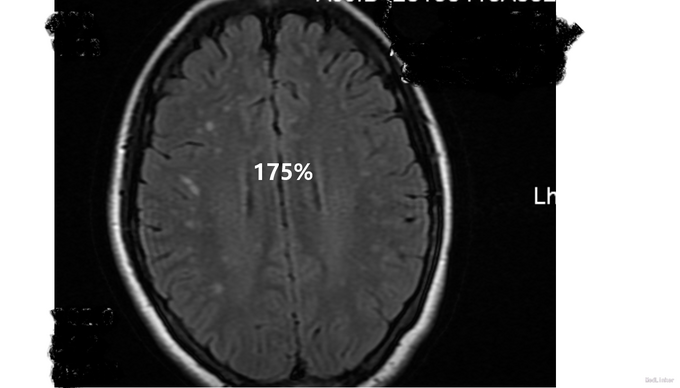

查体:生命体征平稳,心律齐,未闻及病理性杂音,双肺呼吸音清,未闻及干湿罗音。腹软,无压痛及反跳痛,肝脾肋下未及,双下肢不肿。3月21日神经系统检查:意识清楚,回答问题有时不切题,记忆力下降,定向力可,存在幻听,双侧瞳孔等大等圆,光反射灵敏,双侧鼻唇沟对称,伸舌居中,四肢肌力、肌张力、腱反射正常,病理征未引出。颈软,Kernig征阴性,Brudzinski征阴性。3月26日神经系统检查:意识模糊,不能言语,查体不能配合,双侧瞳孔等大等圆,直径约3mm,双侧光反射均迟钝,眼球活动不配合,双侧鼻唇沟尚对称,伸舌不能配合,双上肢肌张力高,四肢肌力查体不配合,可见自主活动,肌力在3级以上。病理征阴性,左侧趾反射弱,疼痛刺激反应减弱,颈强2指,Kernig征双侧阳性,Brudzinski征阴性。 脑脊液检查示:3月26日脑脊液检查:Pro 0.3g/L WBC 48 *10^6抗酸、墨汁染色均为阴性。脑脊液抗NMDA抗体IgG阳性,血抗NMDA抗体IgG 阳性,颅脑MRI平扫+flair+DWI:双侧额颞顶叶皮层下多发异常信号。肿瘤标志物检测(—)。我院子宫肌附件B超提示:右侧卵巢囊肿。